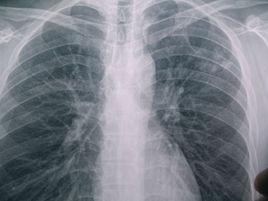

雙肺肺炎

胸片右圖可見雙肺斑片狀陰影

陰影模糊不清

雙肺呈毛玻璃狀